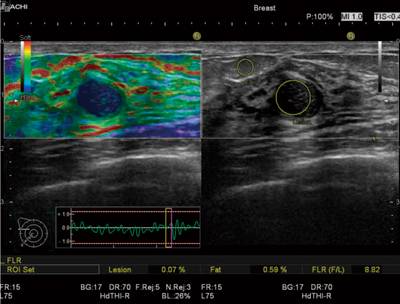

その問題を解決するために,われわれは,ROI設置にかかわる操作をサポートする“Assist Strain Ratio”を開発しました。エラストグラフィを描出した後,検査者が腫瘤の中心を指定すると,腫瘤と脂肪層に自動でROIが設置され,FLR値が算出されます(図1)。このAssist Strain Ratioにより,検査者間での計測誤差を低減するだけでなく,計測にかかわる操作を簡略化することで,検査効率を向上できると期待されています。

図1 Assist Strain Ratio使用例

(画像ご提供:川崎医科大学附属川崎病院・中島一毅先生)